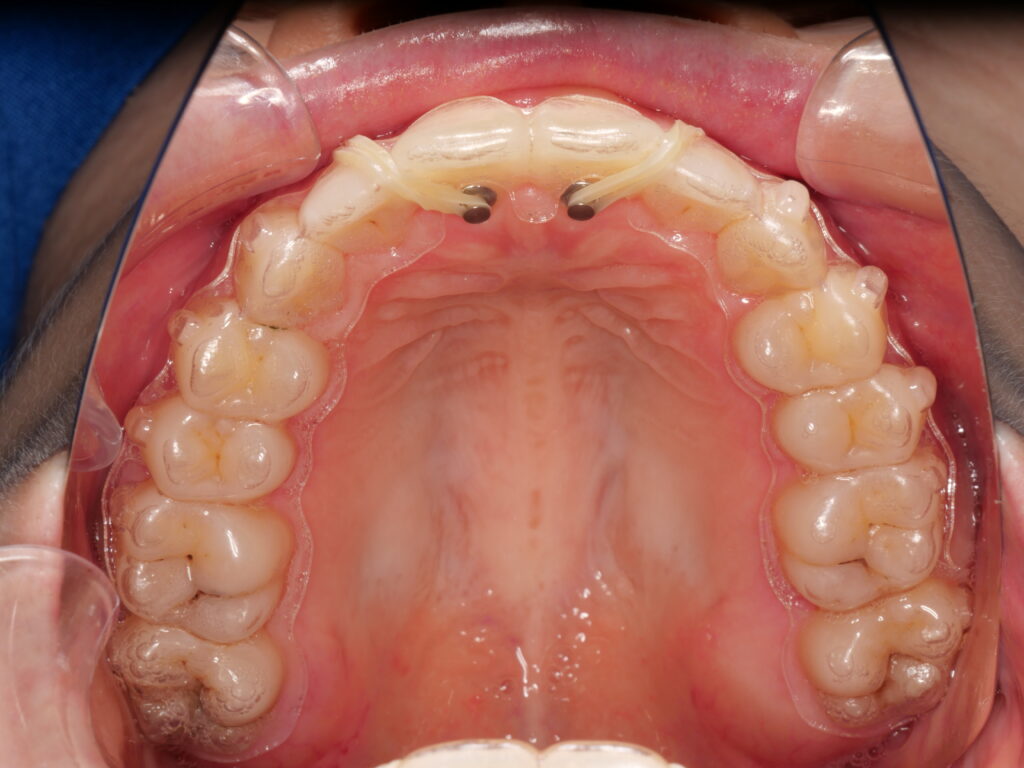

当院では、Brava(ブラーバ)という国内でも取り扱いの少ない装置を採用しております。

これまでのようにワイヤーで全体をつないで歯を動かすのではなく、1本1本の歯に直接、独立した力をかけて動かすという革新的なシステムを採用しています。

すべての装置が歯の裏側(舌側)に装着されるため、見た目ではほとんど矯正していることがわかりません。従来の舌側矯正では、歯の裏側にブラケットとワイヤーを固定して歯を並べていましたが、Bravaでは各歯に個別の「アクティブブラケット」を装着し、それぞれが独立して歯を動かす構造になっています。

治療前にスキャンした3Dデータを元にAIが歯の動きと力のかかり方を設計し、そのデータをもとに、患者様一人ひとりに合わせたカスタムメイドによる装置が作られます。

- 表側矯正に比べて通院頻度が少なくて済む